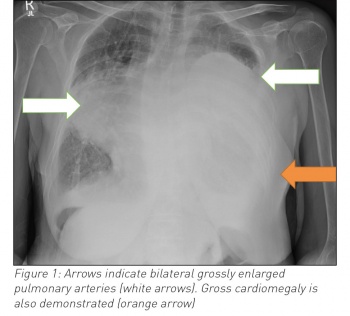

Blood work showed a neutrophilia, hypochromic anaemia, elevated C-reactive protein and an acidotic type two respiratory failure. A chest radiograph was significant for an opacity in the lower two-thirds of the left lung field and a second opacity in the right mid-zone. Given the woman’s past history the differential included right-sided pneumonia, left-sided pleural effusion and cardiomegaly, or hypertrophied pulmonary arteries.

A computed tomography scan confirmed grossly hypertrophied pulmonary vasculature.